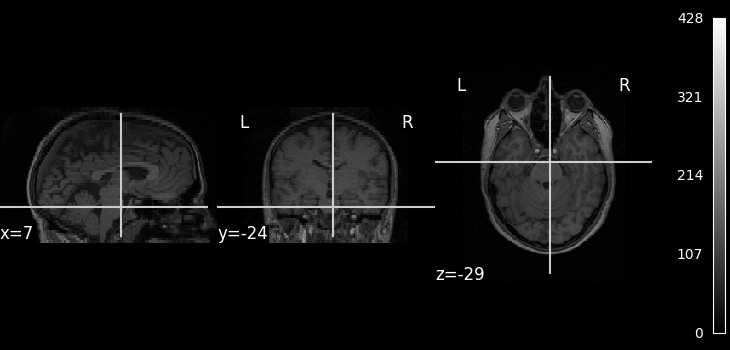

We can display the mean functional image and the subject’s anatomy:

from nilearn.image import mean_img

from nilearn.plotting import plot_anat, plot_img, plot_stat_map, show

fmri_img = subject_data.func

mean_img = mean_img(subject_data.func[0])

plot_img(mean_img, cbar_tick_format="%i")

plot_anat(subject_data.anat, cbar_tick_format="%i")

show()